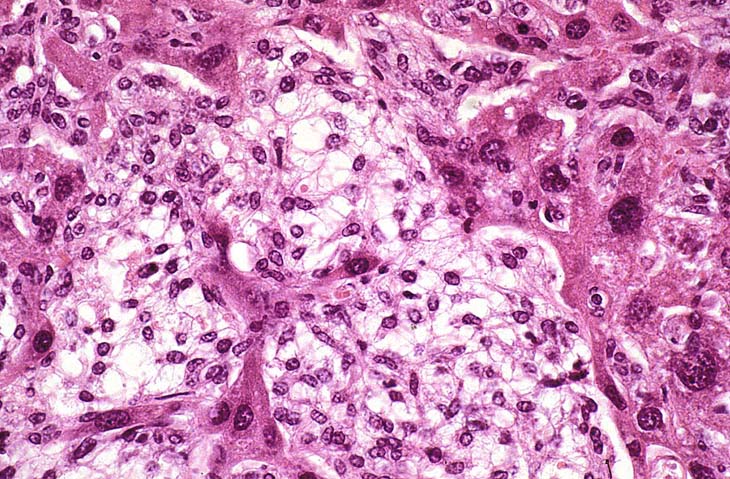

The proliferating stellate cells have a myxomatous appearance in some areas and have caused atrophy of hepatic cords.